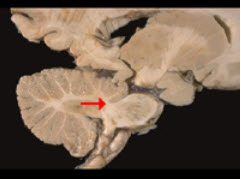

如图箭头所示为小脑哪个部位( )

A:小脑扁桃体

B:小脑下脚

C:小脑中脚

D:小脑上脚

E:小脑蚓部